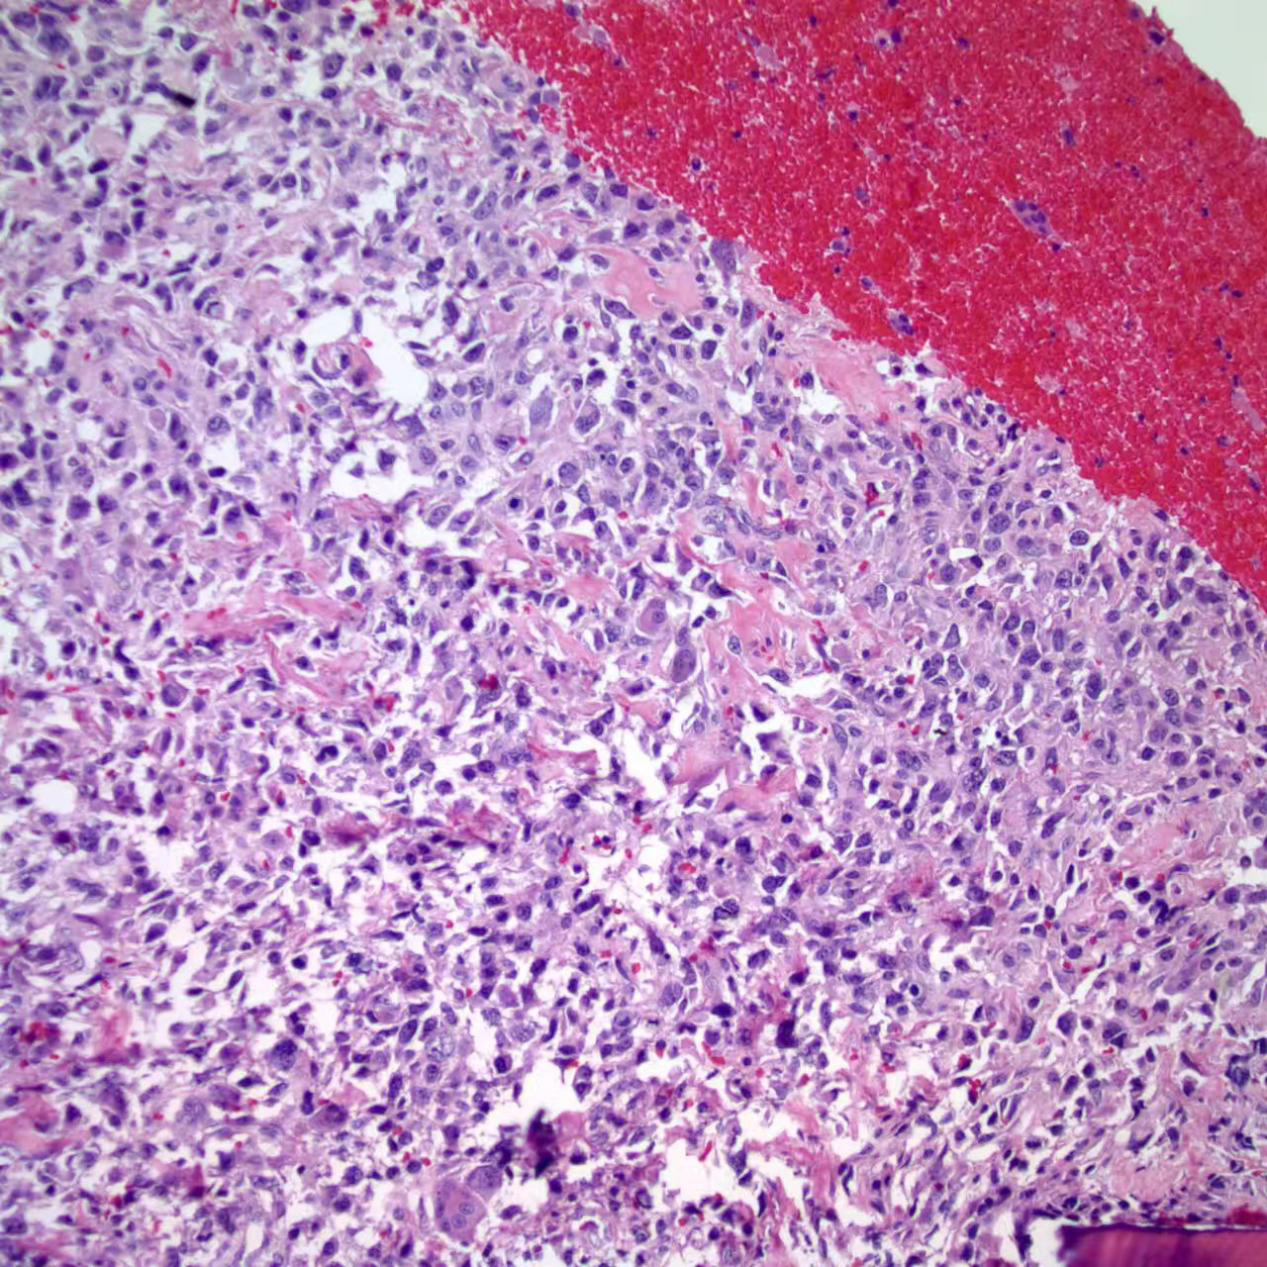

骨肉瘤的梭形瘤细胞正在制造淡红色的类骨质.

普通型骨肉瘤